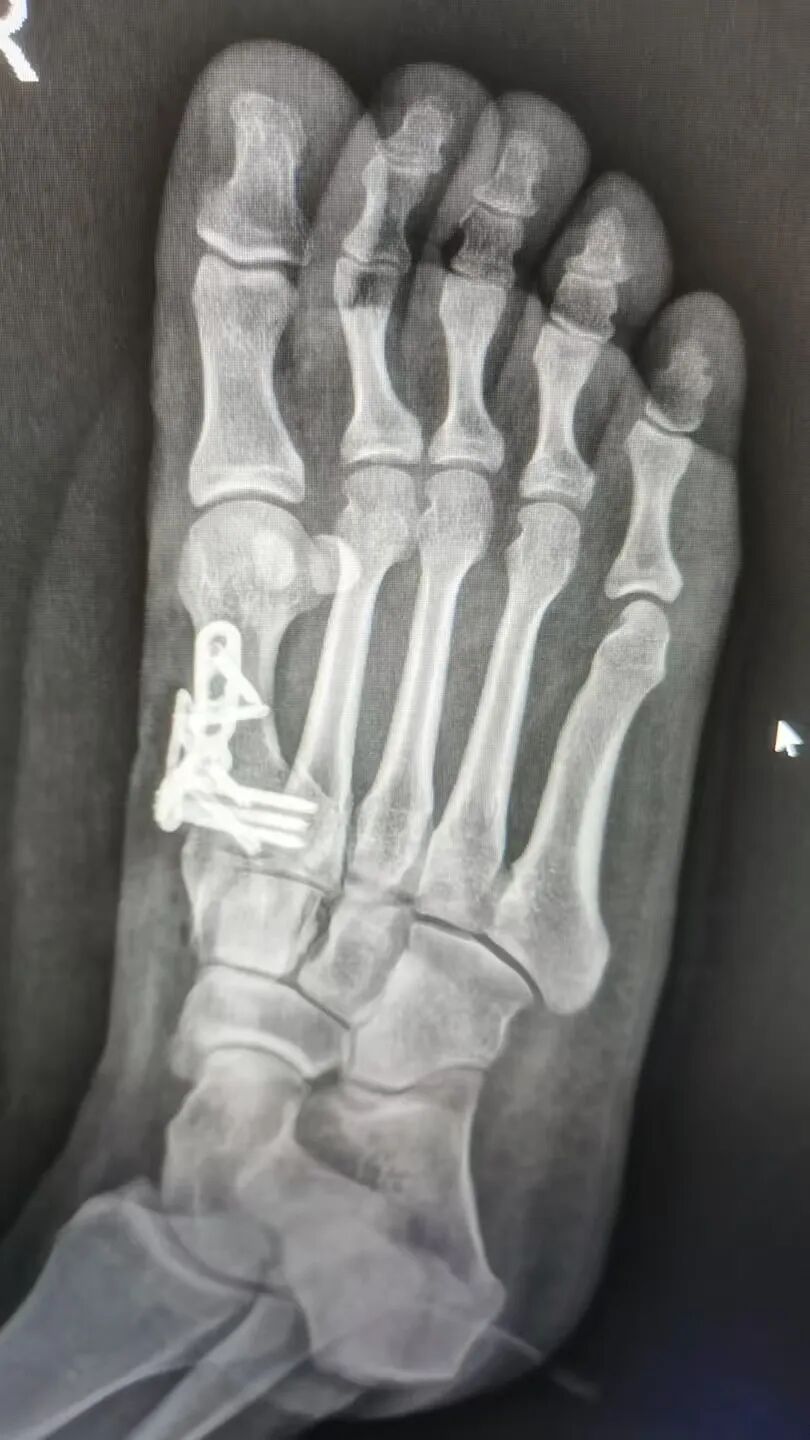

经过两个礼拜的精心治疗与护理,唐女士的手术非常成功,病情得到了显著改善而康复出院。为表达感激之情,她特意写下这封感谢信,字里行间满是对医护人员专业素养的认可和人文关怀的动容。

△术后